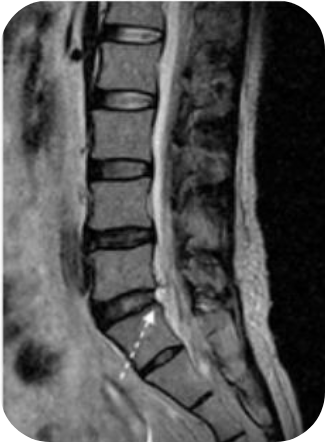

PELD

척추내시경

이 수술법이 처음 나온 지는 20년이 넘었습니다만 최근 들어 기기와 기술의 발전으로 각광을 받게 되었습니다. 피부에 약 7 mm 크기의 내시경을 넣어 수술을 하는 것으로 수술 후 회복이 매우 빠르다는 장점이 있습니다. 과거에는 터져 나온 디스크를 처리하지 못하는 한계를 보였으나 이제는 많이 발전하여 디스크의 여러 유형을 처리할 수 있어 수술의 성공률이나 환자의 만족도도 많이 높아졌습니다.

- 추간판탈출증